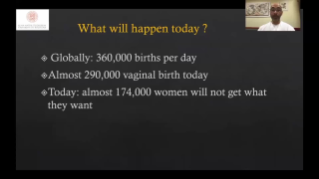

Using ultrasound as part of an optimised OBG workflow can support large patient volumes for women's health screening. For example, central nervous system (CNS) malformations are one of the most common congenital abnormalities. Due to imaging conditions such as poor fetal position, the median sagittal plane (MSP) is particularly difficult to obtain from 2D ultrasound. Therefore, automated detection and measurements can greatly enhance scanning efficiency.